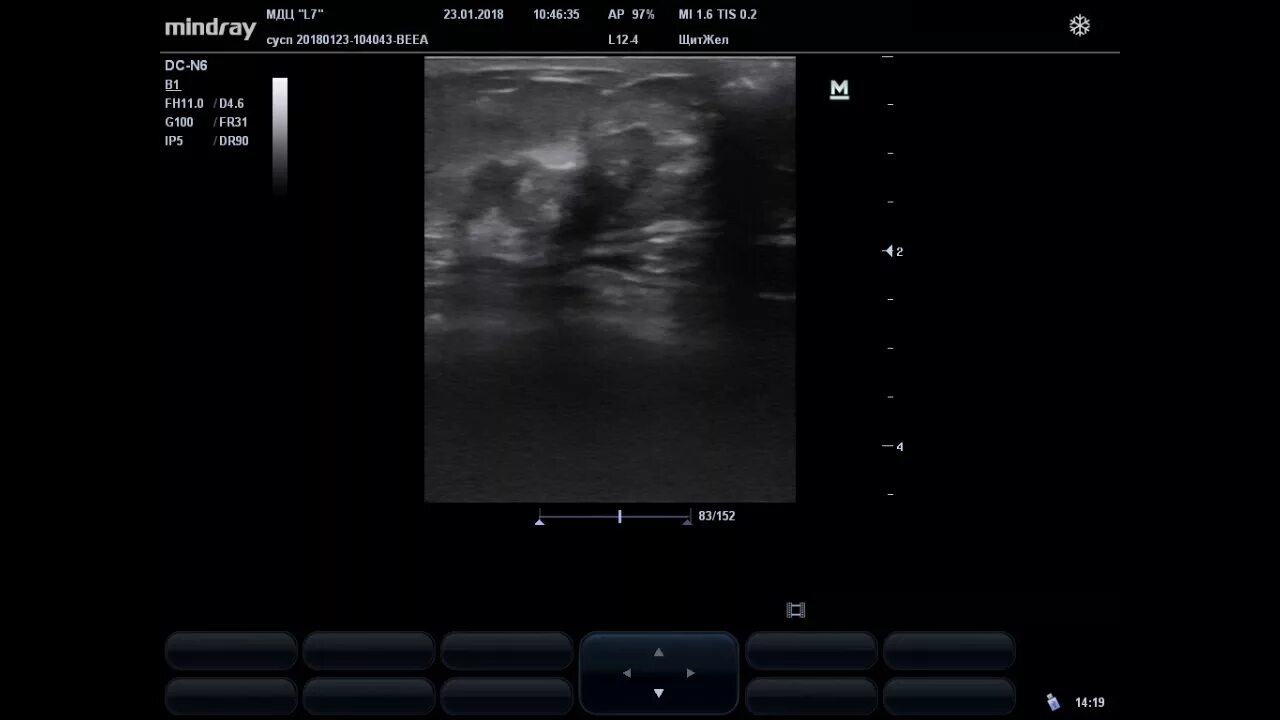

Узи молочных киров